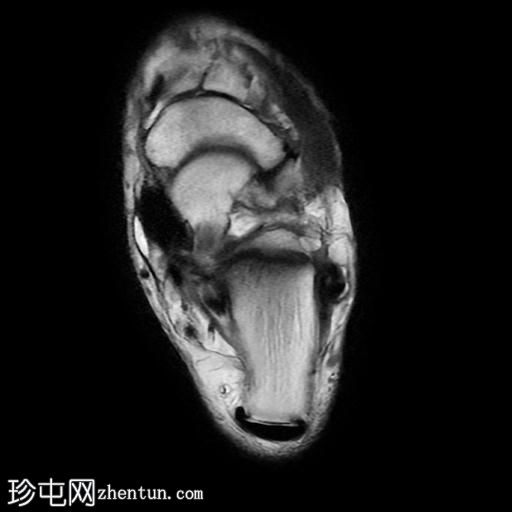

矢状位

PD脂肪抑制序列

跟骨前突延长增宽,与舟骨形成不规则关节,形似“食蚁兽

鼻

”。

该异常跟舟关节处可见关节下骨髓水肿。此外,舟骨内外侧径增宽,向外侧逐渐变细,并与增大的跟骨前突形成关节。

距舟关节轻度积液,并可见边缘骨赘。